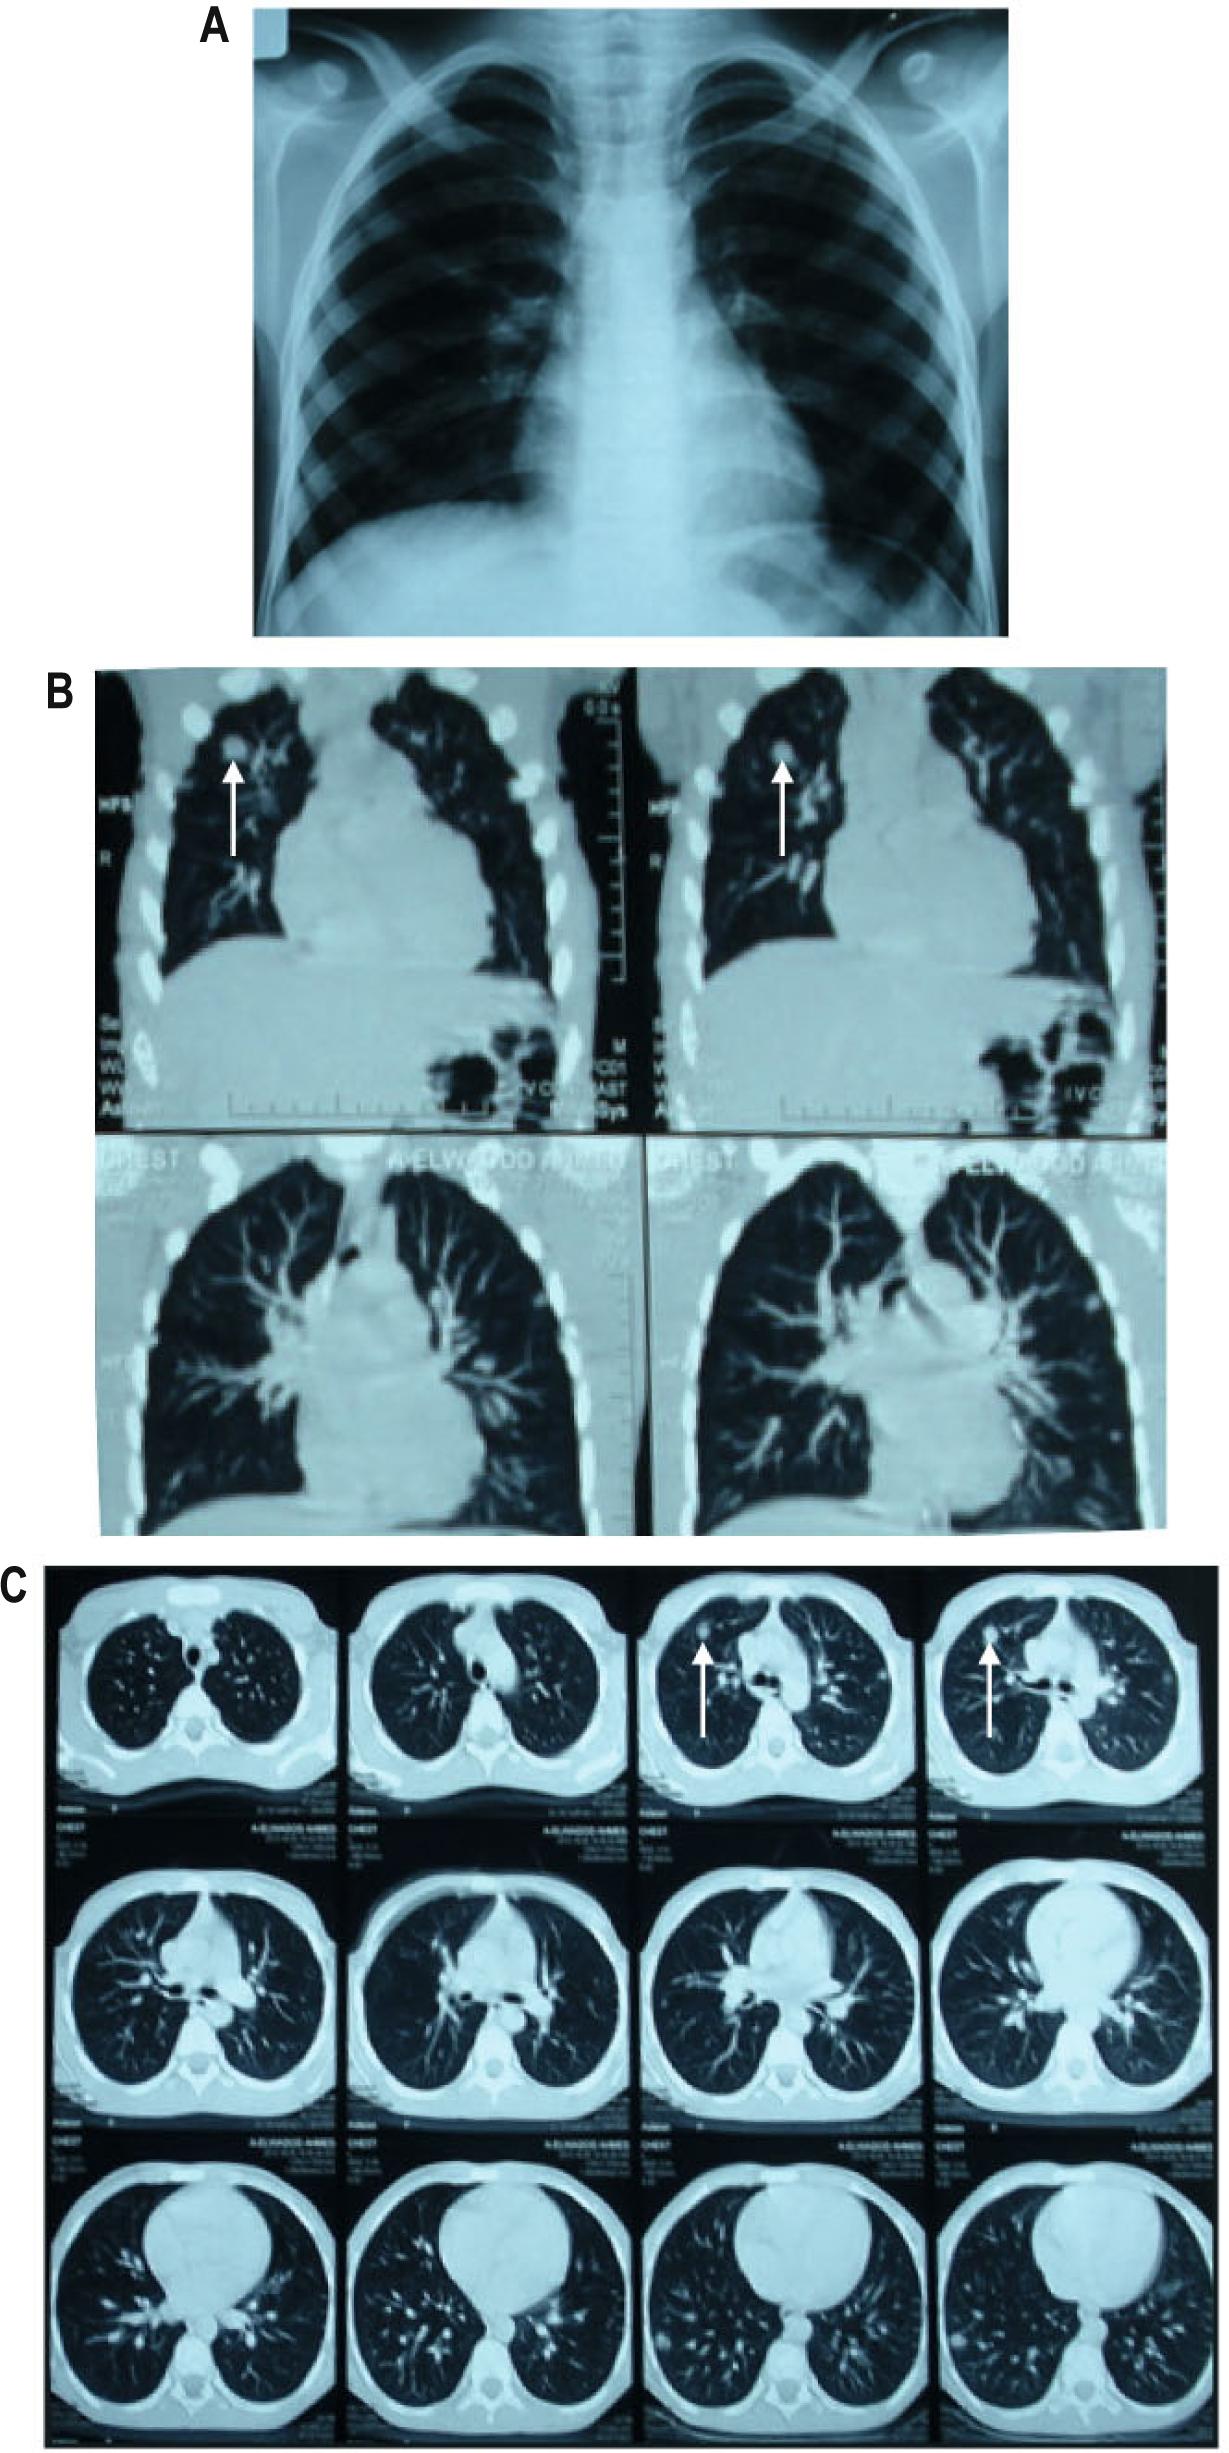

Chest X-ray showed an infiltrative shadow in both middle and lower lung fields mainly in the right lung (Fig. 1A). Using Post-Contrast Spiral CT Chest (Fig.1B and C), the chest was scanned in 10mm continuous slices from the rout of the neck caudally to the suprarenal glands. Lung CT showed bilateral multiple sharply defined, smoothly marginated, rounded pulmonary nodules measuring less than 1 cm in diameter with centrilobular pattern and characteristic tree in bud sign. The most predominant two pulmonary nodules demonstrated mainly in the anterior segment of upper lobe and lateral segment of lower lobe of right lung field respectively (indicated by arrows). Chest CT showed clearly patent airways down to the segmental bronchi i.e no endoluminal lesion or extrinsic compression. There is no pleural thickening or effusion and no hilar or mediastinal lymphadenopathy.

(A) Chest X-ray film showing an infiltrative shadow in both the middle and lower lung fields mainly in the right lung. (B) and (C) CT scan images showing bilateral multiple intra-pulmonary focal lesions. The most predominant two pulmonary nodules demonstrated mainly in the anterior segment of upper lobe and lateral segment of lower lobe of right lung field respectively.

This case confirmed the findings of chest radiography and computed tomography demonstrated in the earlier publications (Inoue et al., 2002; Izumikawa et al., 2011). They have reported that granulomas or abscesses could appear as rounded nodules that are similar in appearance to other inflammatory lesions in chest radiography and lung CT. The sonographic findings of hepatic VLM syndrome were multiple ill-defined oval or elongated small nodular lesions scattered in the liver parenchyma (Holland et al., 2006; Ko et al., 2015). In this study, CT enabled better detectability and estimation of the distribution characteristics and the extent of the lesions than did chest radiography. Furthermore, CT represented unexpected features that chest radiography did not depict. Such features included reactive infiltration, parenchymal destruction, and granuloma or abscess formation.